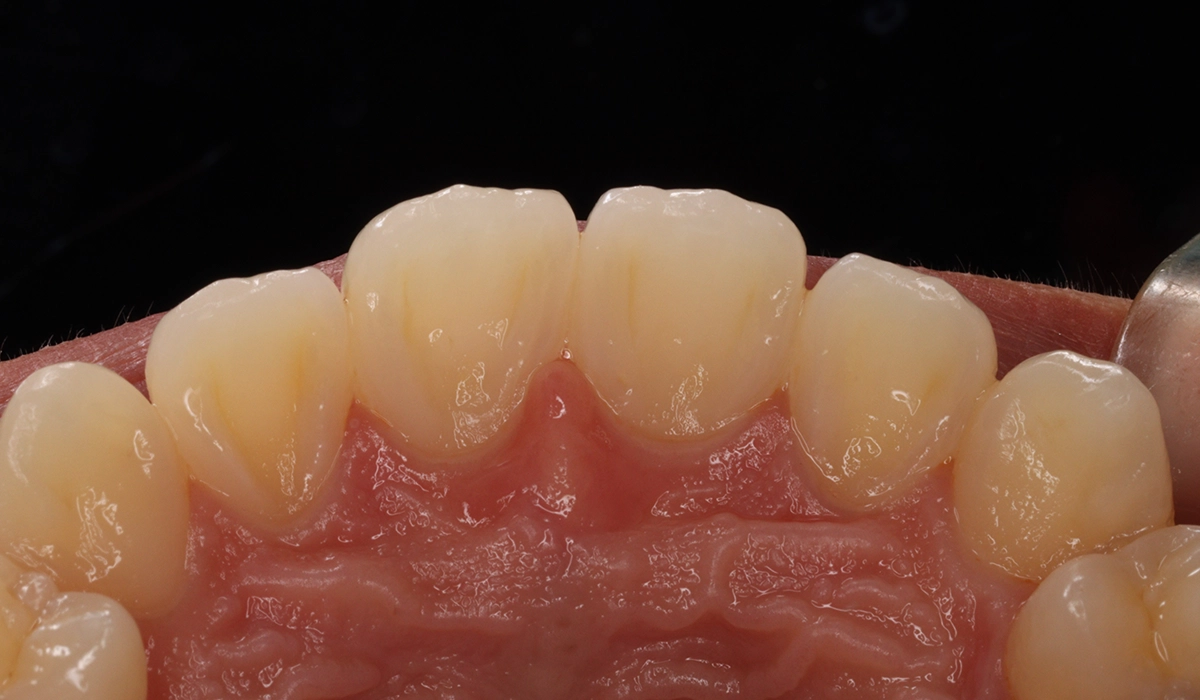

術前:上顎前歯部寄り

術後:前歯部あおり